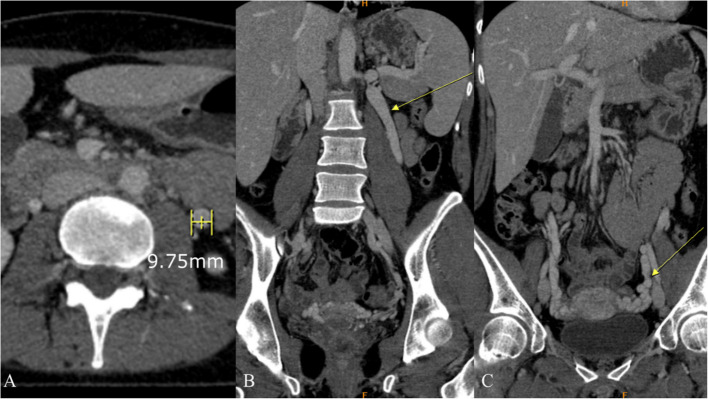

胡桃夹子综合征(NCS)是一种相对罕见的血管疾病,其特征是左肾静脉(LRV)受压,导致多种非特异性症状,包括血尿、侧腹疼痛、精索静脉曲张和盆腔充血综合征。LRV受压来源可分为前、后两种:前路NCS发生于LRV受压于主动脉与肠系膜上动脉之间,后路NCS发生于主动脉与脊柱之间。尽管诊断方式有了进步,包括多普勒超声、计算机断层扫描、磁共振成像和侵入性技术,如静脉造影术,但仍然没有全球公认的诊断算法,导致诊断不一致。此外,由于缺乏标准化的治疗指南,前路NCS的最佳治疗仍然是一个有争议的话题。虽然在儿童人群中通常推荐保守治疗,但侵入性治疗——包括LRV转位和肾脏自体移植等手术选择,以及介入放射治疗(如支架置入术)——存在支架移位、再狭窄和材料长期耐用性等挑战。尽管如此,3d打印支架的出现为患者特异性治疗提供了潜在的改进,特别是在儿科人群中,但其临床疗效和安全性仍在调查中。本文简要介绍了目前关于前路NCS治疗的讨论,强调需要标准化的诊断算法、多学科方法和持续的技术进步来完善治疗可能性和策略。进一步的研究对于解决这些争议和就最佳做法达成共识至关重要。

Nutcracker syndrome (NCS) is a relatively uncommon vascular condition characterized by compression of the left renal vein (LRV), resulting in a variable spectrum of nonspecific symptoms, including hematuria, flank pain, varicocele, and pelvic congestion syndrome. NCS can be classified into anterior and posterior types regarding the origin of LRV compression: anterior NCS occurs when LRV is compressed between the aorta and superior mesenteric artery, whereas posterior NCS involves LRV compression between the aorta and the spine. Despite advancements in diagnostic modalities, including Doppler ultrasound, computed tomography, magnetic resonance imaging, and invasive techniques like phlebography, there is still no globally accepted diagnostic algorithm, leading to inconsistencies in diagnosis. Moreover, due to the lack of standardized treatment guidelines, the optimal management of anterior NCS remains a topic of debate. While conservative management is usually recommended in the pediatric population, invasive treatments-including surgical options like LRV transposition and renal autotransplantation, as well as interventional radiology procedures like stenting, present challenges such as stent migration, restenosis, and long-term material durability. Nevertheless, the emergence of 3D-printed stents offers potential improvements in patient-specific treatment, particularly in the pediatric population, yet their clinical efficacy and safety remain under investigation. This brief communication addresses the current discussions regarding anterior NCS management, emphasizing the need for standardized diagnostic algorithms, a multidisciplinary approach, and continued technological advancements to refine treatment possibilities and strategies. Further research is critical to resolve these controversies and establish a consensus on best practices.